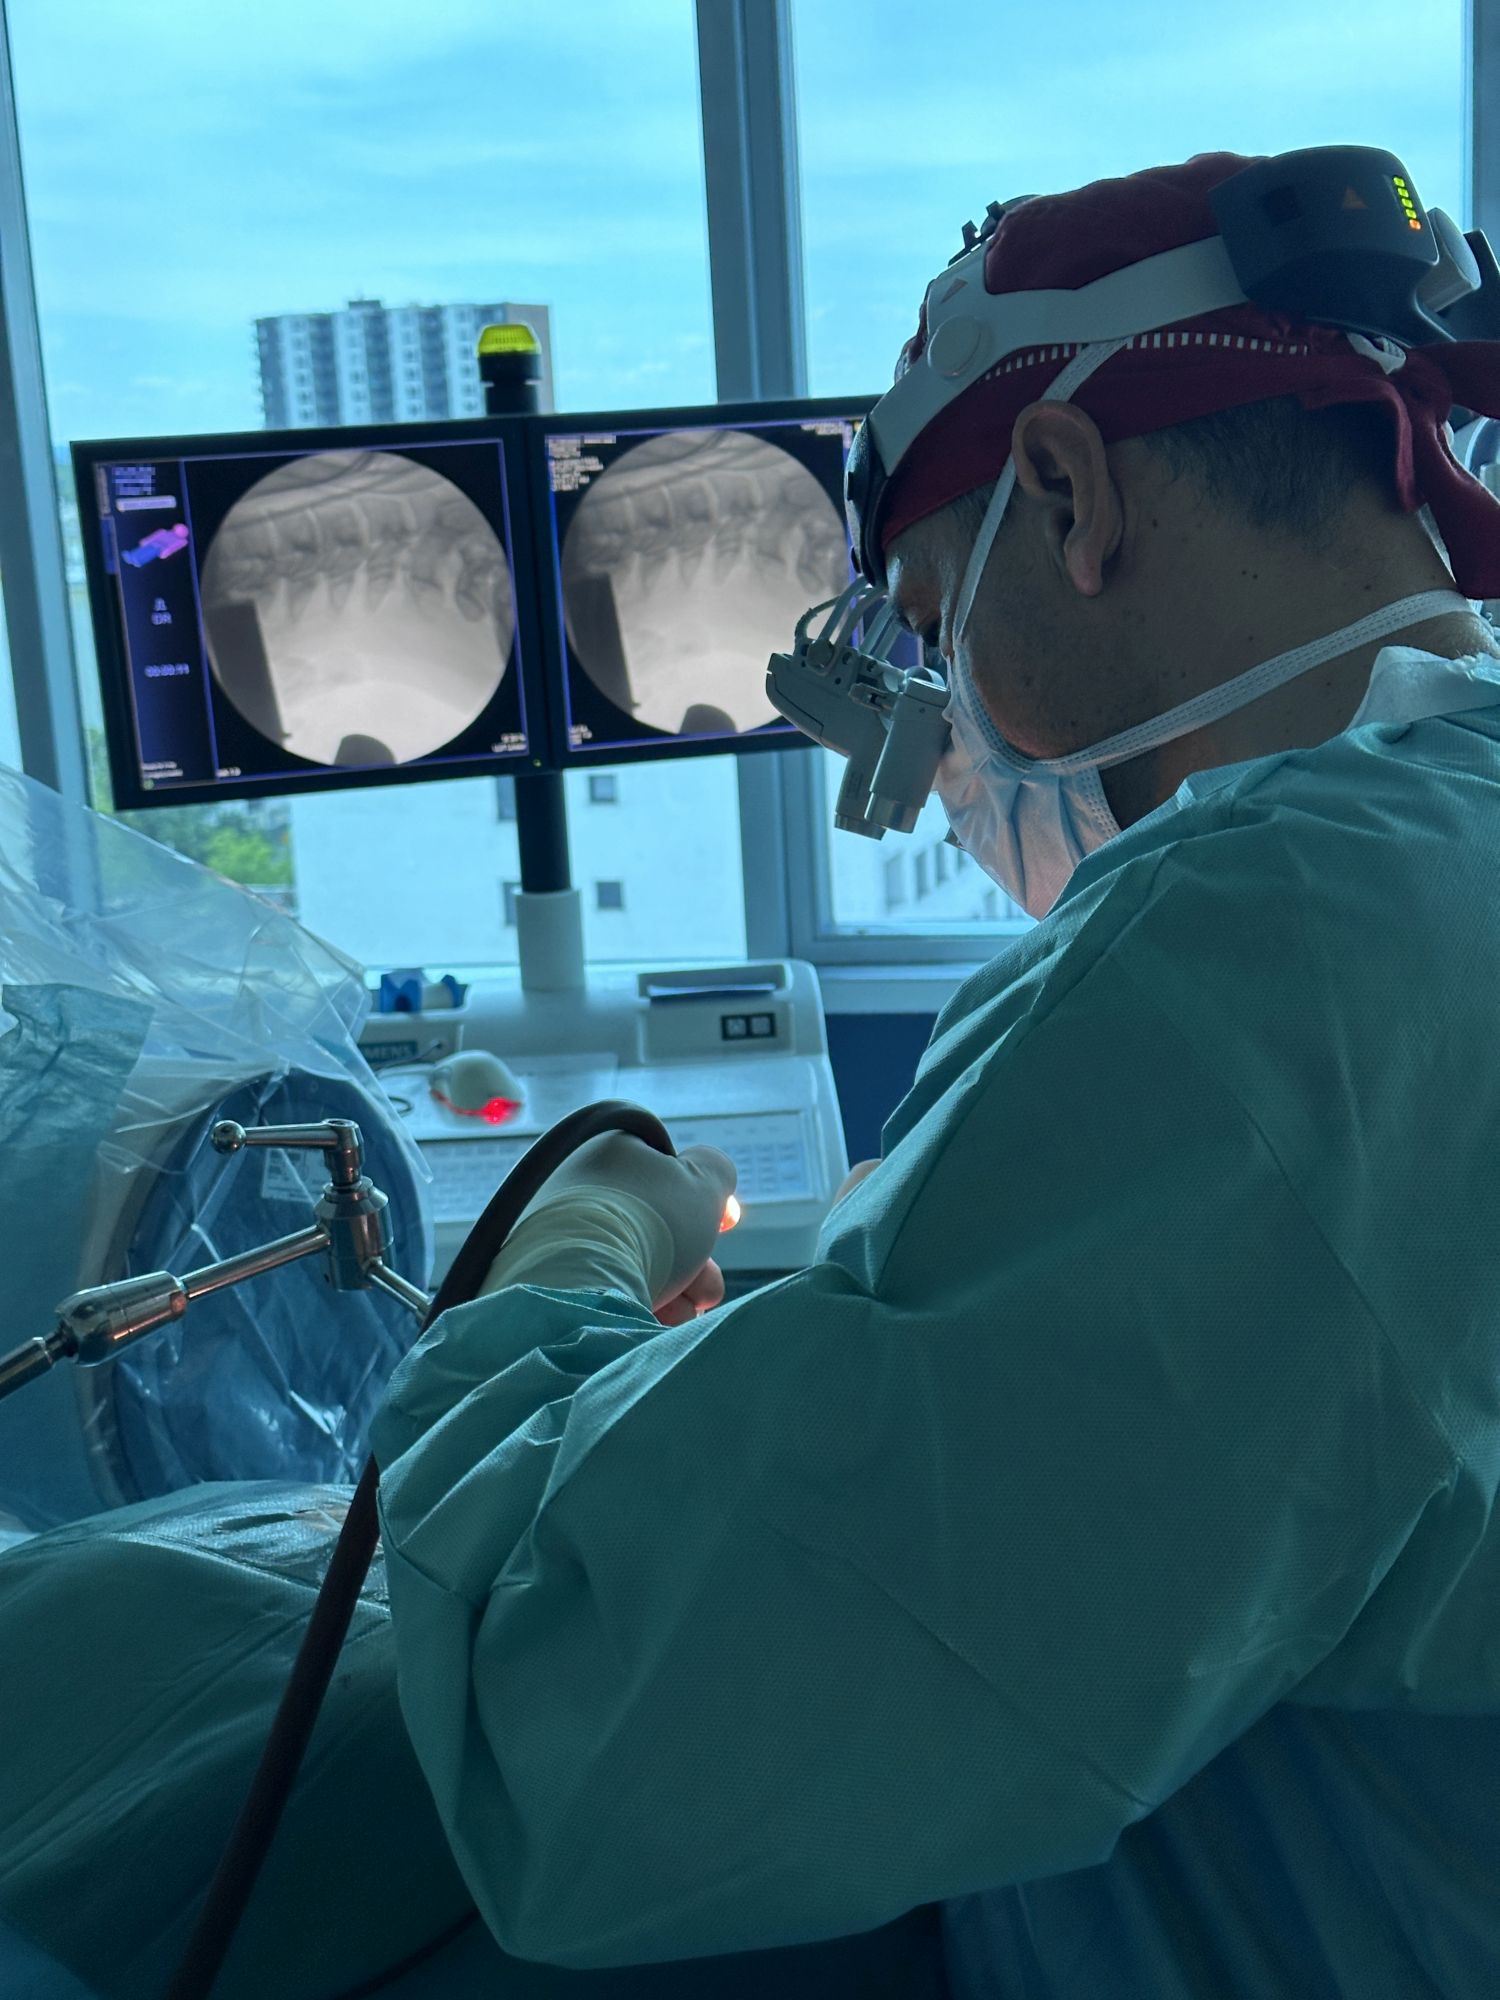

Ponosni smo na našu predanost i vrhunske rezultate u neurokirurgiji kralježnici. U zadnjih nekoliko dana naš izvanredni tim izveo je i dvije napredne i zahtjevne operacije kralježnice koje su pacijentima donijele olakšanje i poboljšanu kvalitetu života – METRx mikro-endoskopsku stražnju dekompresiju vratne kralježnice, te miniOpen TLIF spinalnu fuziju.

Naše iskustvo, znanje i tehničke mogućnosti omogućuju nam izvođenje najsloženijih zahvata s visokom stopom uspjeha. Zahvaljujući naprednoj tehnologiji i kontinuiranoj edukaciji naši neurokirurzi pružaju najbolju moguću skrb. U nastavku pogledajte slike koje prikazuju preciznost i inovativnost naših zahvata.